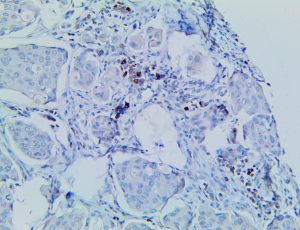

It is the ICU physician who is most likely to witness one of the deadliest manifestations of the abnormal immunological response, the cytokine storm syndrome (CSS). This response is also referred to by some as the cytokine release syndrome (CRS). CSS is characterized by continuous activation and expansion of macrophage and lymphocyte populations, which secrete large amounts of cytokines, causing the cytokine storm. This massive cytokine release is akin to hemophagocytic lymphohistiocytosis (HLH) disease, a syndrome characterized by initial unchecked and persistent activation of cytotoxic T lymphocytes and NK cells.

Clinical and laboratory manifestations of HLH include fever, enlarged liver and/or spleen, neurologic dysfunction, coagulopathy, liver dysfunction, cytopenias (i.e., low levels of erythrocytes, leukocytes, and/or platelets), hypertriglyceridemia, hyperferritinemia, hemophagocytosis, and eventually diminished NK cell activity as the immune system becomes progressively paralyzed. HLH can be familial (primary HLH) or secondary to another disease process (sHLH), such as rheumatic disease, in which it is referred to as macrophage activation syndrome (MAS, characterized by elevated ferritin).